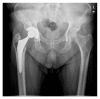

More than twenty years ago, hydroxyapatite (HA), calcium phosphate ceramics, was introduced as a coating for cementless hip prostheses. The choice of this ceramic is due to its composition being similar to organic apatite bone crystals. This ceramic is biocompatible, bioactive, and osteoconductive. These qualities facilitate the primary stability and osseointegration of implants. Our surgical experience includes the implantation of more than 4,000 cementless hydroxyapatite coated hip prostheses since 1990. The models implanted are coated with HA in the acetabulum and in the metaphyseal area of the stem. The results corresponding to survival and stability of implants were very satisfactory in the long-term. From our experience, HA-coated hip implants are a reliable alternative which can achieve long term survival, provided that certain requirements are met: good design selection, sound choice of bearing surfaces based on patient life expectancy, meticulous surgical technique, and indications based on adequate bone quality.